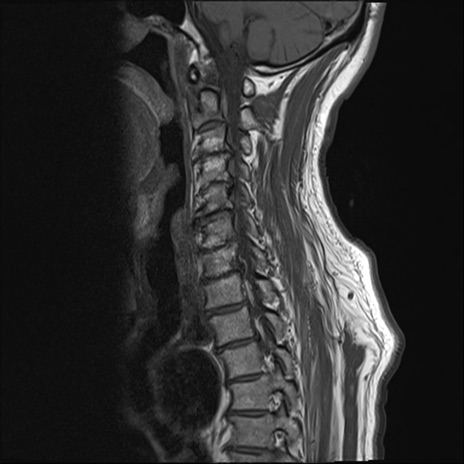

【整形】TIPS症例7 頚椎MRI T1WI(矢状断像)

頚椎MRI

T2WI(矢状断像)